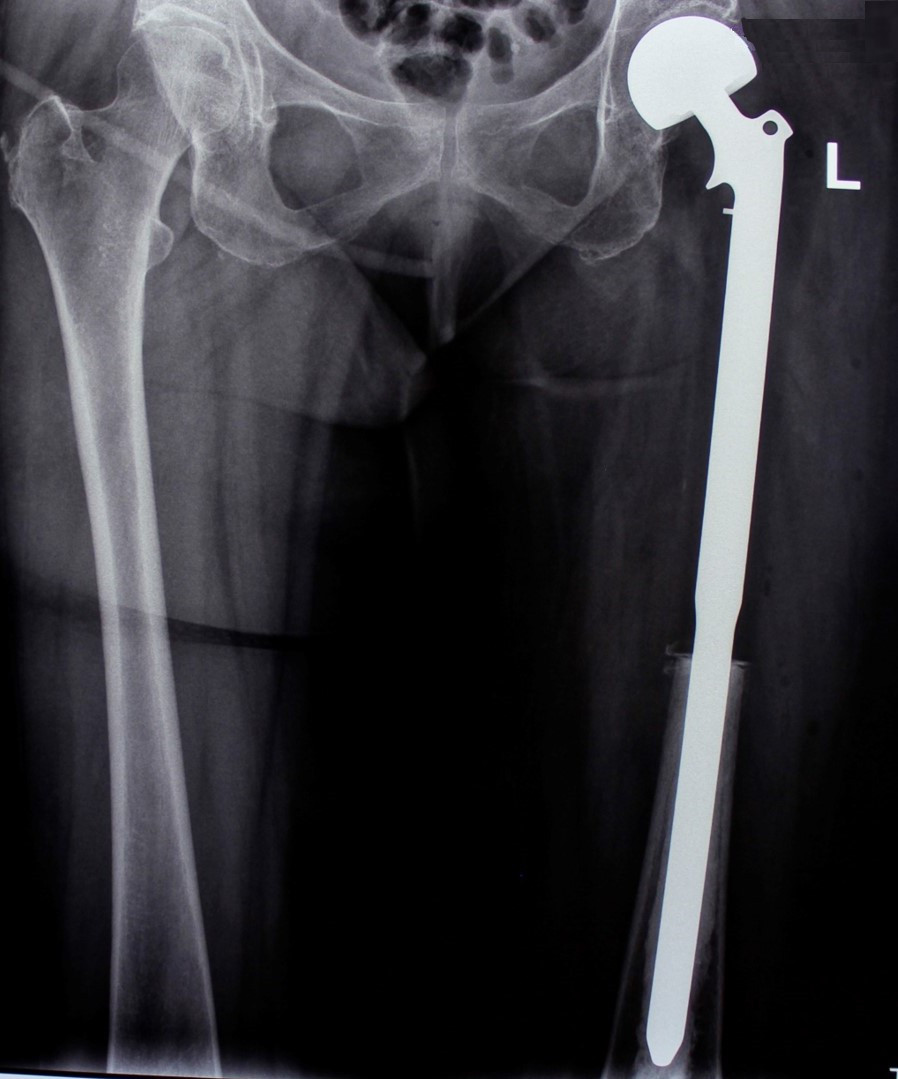

После проведения предоперационной химиотерапии пациент был прооперирован – была произведена сегментарная резекция верхней трети бедренной кости, образовавшийся дефект был замещен индивидуальным биполярным эндопротезом бедренной кости и тазобедренного состава, изготовленным на заказ в Европе. В результате проведения органосохранного лечения удалось сохранить функционирующую конечность пациента.

После операции